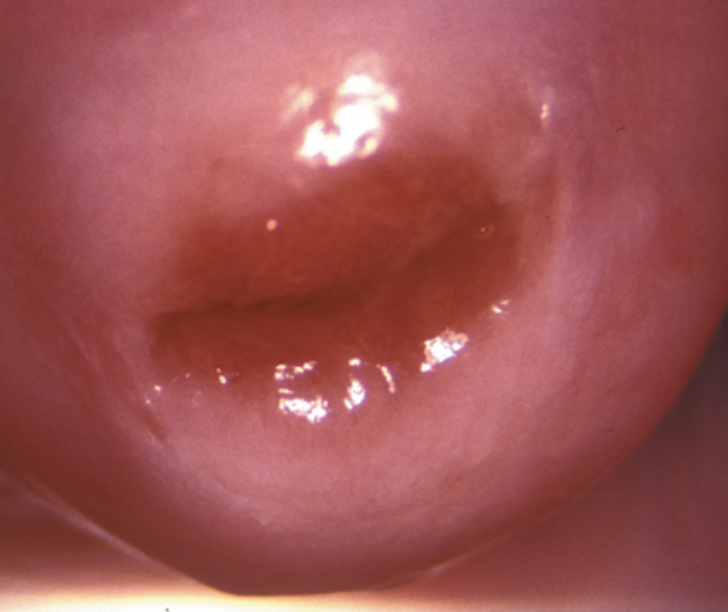

what will examination of the cervix show in cervical ectropian?

well-demarcated border between the redder, velvety columnar epithelium extending from the os and the pale pink squamous epithelium of the endocervix

border = tranformation zone